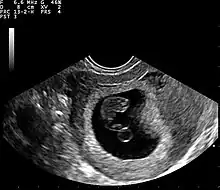

Ultrasound

Obstetric ultrasonography may also be used to detect and diagnose pregnancy. It is very common to have a positive at-home urine pregnancy test before an ultrasound. Both abdominal and vaginal ultrasound may be used, but vaginal ultrasound allows for earlier visualization of the pregnancy. With obstetric ultrasonography the gestational sac (intrauterine fluid collection) can be visualized at 4.5 to 5 weeks gestation, the yolk sac at 5 to 6 weeks gestation, and fetal pole at 5.5 to 6 weeks gestation. Ultrasound is used to diagnose multiple gestation, which cannot be diagnosed based on the presence of hCG in urine or blood.[15] Determination of the gestational age of the embryo/fetus is an additional benefit of ultrasound compared to hCG tests.[16]